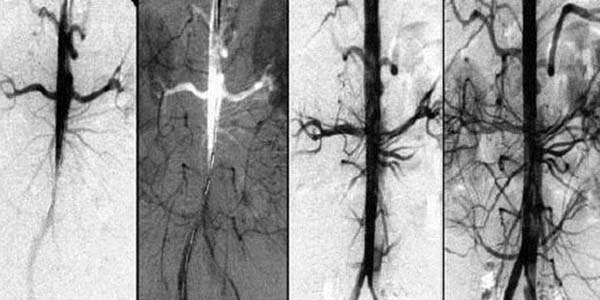

La circulación sanguínea se restaura sistémicamente – en todos los vasos, arterias y capilares.